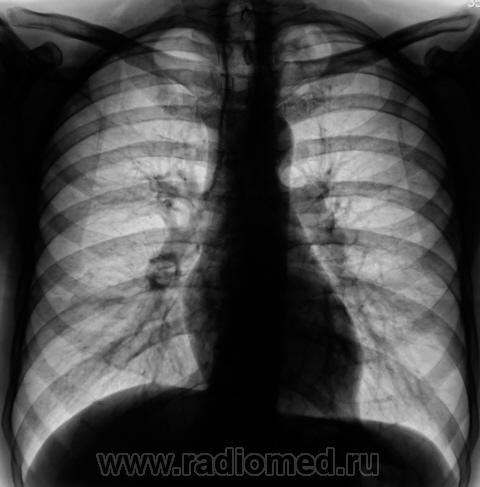

Пол пациента: Мужской пол Тип патологии: Другое Область исследования: Грудная клетка и верхние дыхательные пути Методы исследования: Rg При расшифровке цифровых флюорограмм пациент "взят на контроль". Сомнения вызвала левая верхушка. Произведено стандартное дообследование. Ваше мнение коллеги? Пнд, 28/09/2009 - 19:58 #1 Sergo Не на сайте Был на сайте: 14 лет 3 месяцев назад Зарегистрирован: 26.06.2009 - 18:42 Публикации: 41 Это благодарный пациент таким образом отразил свою большую любовь к Вам в виде маленького сердечка. Наверное дело было на День Св. Валентина. Сб, 02/09/2017 - 21:53 #2 Катенёв Валенти... Не на сайте Был на сайте: 7 лет 2 недели назад Зарегистрирован: 22.03.2008 - 22:15 Публикации: 54876 А случай то интересный... Сб, 02/09/2017 - 21:58 #3 colombina Не на сайте Был на сайте: 1 год 7 месяцев назад Зарегистрирован: 07.07.2016 - 16:28 Публикации: 478 Sergo wrote: Это благодарный пациент таким образом отразил свою большую любовь к Вам в виде маленького сердечка. Наверное дело было на День Св. Валентина. + 1. А если по-серьезному, то вероятнее ретенционная киста. Сб, 02/09/2017 - 22:09 #4 Катенёв Валенти... Не на сайте Был на сайте: 7 лет 2 недели назад Зарегистрирован: 22.03.2008 - 22:15 Публикации: 54876 Вы правы уважаемая коллега. Классика жанра. Вс, 03/09/2017 - 17:57 #5 Nikolas Не на сайте Был на сайте: 1 месяц 3 недели назад Зарегистрирован: 21.12.2010 - 20:37 Публикации: 4559 Похоже на ретенционную кисту. Заполненная брохиальная киста легкого представляет расширенный бронх, чаще 3-5 порядка. А здесь? Как легко спутать с очаговым туберкулёзом, тем более имеются рядом мелкие очаги. Как доказали, что это ретенционные кисты? Сб, 02/09/2017 - 22:50 #6 Катенёв Валенти... Не на сайте Был на сайте: 7 лет 2 недели назад Зарегистрирован: 22.03.2008 - 22:15 Публикации: 54876 Nikolas wrote: Как легко спутать с очаговым туберкулёзом, тем более имеются рядом мелкие очаги. Вы чётко видите очаги? Сб, 02/09/2017 - 23:00 #7 Nikolas Не на сайте Был на сайте: 1 месяц 3 недели назад Зарегистрирован: 21.12.2010 - 20:37 Публикации: 4559 Кроме того, тени неоднородной структуры. Так я вижу. Как верифицировали? Приложения: Сб, 02/09/2017 - 23:08 #8 Катенёв Валенти... Не на сайте Был на сайте: 7 лет 2 недели назад Зарегистрирован: 22.03.2008 - 22:15 Публикации: 54876 Пациент был взят на контроль после флюорографии, дообследован. Даже на томограммах остались определенные сомнения. Была назначена консультация фтизиатра. Был на консультации в ОПТД, был поставлен на учёт. Выписка из ОПТД пришла в туб кабинет. Сб, 02/09/2017 - 23:15 #9 Nikolas Не на сайте Был на сайте: 1 месяц 3 недели назад Зарегистрирован: 21.12.2010 - 20:37 Публикации: 4559 Противотуберкулезную химиотерапию проводили? И что написали из ОПТД? Сб, 02/09/2017 - 23:30 #10 Катенёв Валенти... Не на сайте Был на сайте: 7 лет 2 недели назад Зарегистрирован: 22.03.2008 - 22:15 Публикации: 54876 Да. Было инфицирование кисти МБТ.

Похоже на ретенционную кисту. Заполненная брохиальная киста легкого представляет расширенный бронх, чаще 3-5 порядка. А здесь? Как легко спутать с очаговым туберкулёзом, тем более имеются рядом мелкие очаги. Как доказали, что это ретенционные кисты?

Вы чётко видите очаги?

Кроме того, тени неоднородной структуры. Так я вижу.

Пациент был взят на контроль после флюорографии, дообследован.

Даже на томограммах остались определенные сомнения. Была назначена консультация фтизиатра.

Был на консультации в ОПТД, был поставлен на учёт.

Выписка из ОПТД пришла в туб кабинет.

Было инфицирование кисти МБТ.